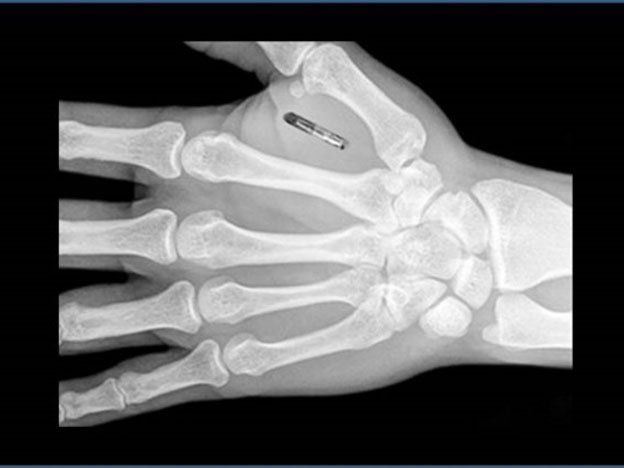

El poder de almacenamiento de estos chips es bastante bajo: ronda los 1024 bytes (1 Kb). Capacidad que los limita únicamente a textos. Y si bien no va a servir para alojar una biblioteca digital con documentos cifrados, este espacio le sobra para activar la alarma del auto o pagar la cuenta del supermercado mediante un conjunto de códigos. Aunque el chip se puede disimular en cualquier parte del cuerpo, lo más práctico es inyectarlo en la mano, en la zona entre el dedo índice y el pulgar. La moda actual dicta que lo ideal es llevar dos: uno en cada extremidad. Su precio oscila entre los $ 400 y los $ 1.200.